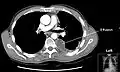

Op een longfoto is pleuravocht zichtbaar als een wit gedeelte op de longfoto.[4] Op een normale thorax foto is de ruimte tussen de viscerale pleura en de pariëtale pleura niet zichtbaar. Wanneer er pleuravocht aanwezig is, is deze ruimte wel zichtbaar. De densiteit van pleuravocht is ongeveer gelijk aan die van water, hierdoor is dit witter op een longfoto in vergelijking met de rest van de long (die meer de densiteit van lucht heeft). Door de hogere densiteit zal pleuravocht zich altijd bevinden op het laagste punt van de thoraxholte en is er een bij horizontale vloeistofspiegel (meniscus).[5] Een longfoto in zijligging (op de zijde waar het pleuravocht zich bevindt) is sensitiever voor pleuravocht. Dit wordt een "decubitus opname" genoemd, bij deze opname wordt een hoeveelheid van 50 ml of meer pleuravocht zichtbaar. Een CT-scan van de borstkas is het meest nauwkeurig voor het bepalen van de aanwezigheid van pleuravocht, maar ook de hoeveelheid en kenmerken van het pleuravocht. Ook echografie kan gebruikt worden om pleuravocht aan te tonen.[6]

CT-scan van de borstholte met linkszijdig pleuravocht. Het pleuravocht bevindt zich meestal in het laagste gedeelte van de thorax, de rugzijde omdat de patiënt in rugligging ligt. -